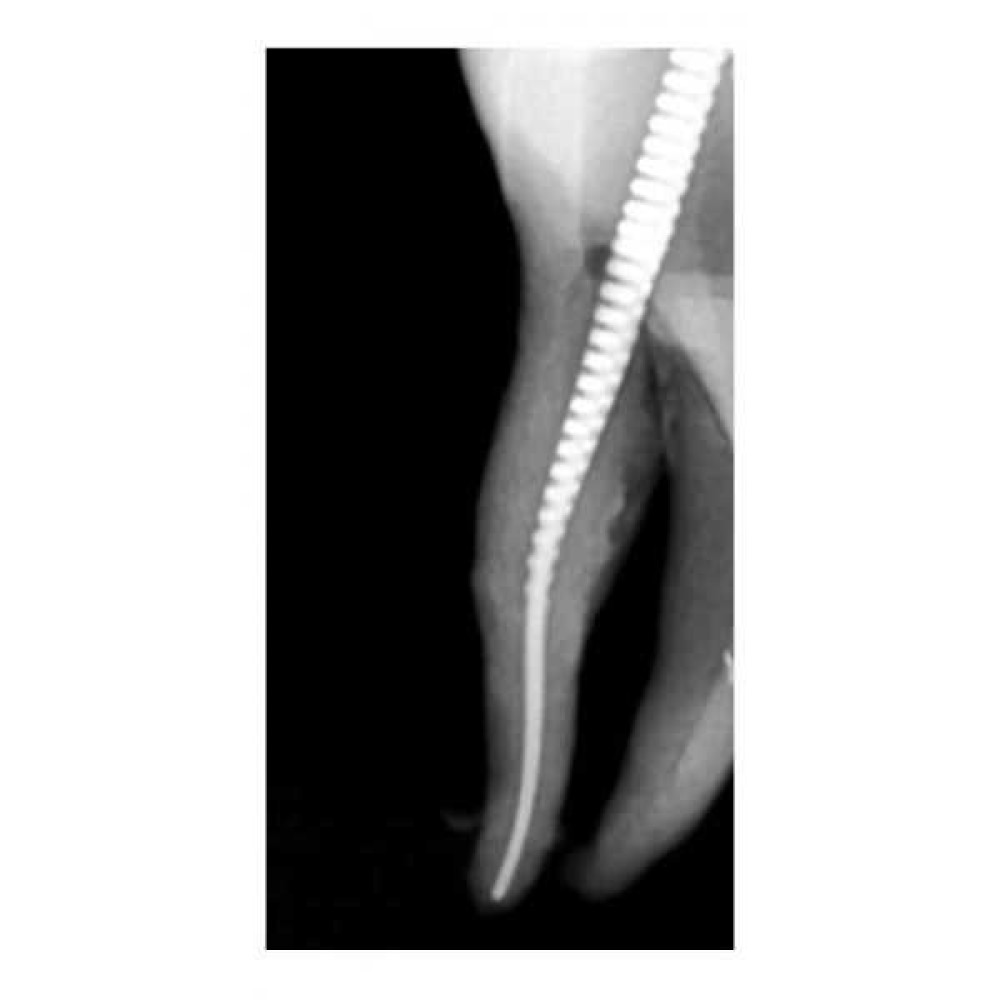

- Гибкий по горизонтали, жесткий по вертикали

- Вертикальное и горизонтальное натяжение уравновешены:возможность приложения усилия в канале любой формы

- Файл стоит из нескольких слоёв витой нержавеющей проволоки

- Многослойная конструкция делает файл пластичным по всей его длине

- Шероховатая поверхность наделяет гибкий файл способностью делать мягкую обработку, деликатно шлифовать и чистить внутреннюю поверхность канала, не меняя при этом его анатомию.

- Благодаря шершавой поверхности и высокой скорости вращения, Gentlefile шлифует стенки корневого канала, а не сверлит и не режет дентин, как это делают NiTi-файлы.

- Кончик файла шириной 0,5 мм имеет фаску под углом 45 градусов и закруглённые края

- Кончик файла пассивен – он гладкий и без острых граней. Такой дизайн позволяет файлу продвигаться по каналу в соответствии с анатомическим строением и предотвращает случаи перфорации.

- Горизонтальная сила (между файлом и стенками канала) и вертикальная сила (позволяющая файлу продвигаться) уравновешены, из-за этого сохраняется естественная анатомия канала

- Вращаясь со скоростью 6500 об/мин. файл разбрасывается центробежной силой - за счет чего обрабатываются стенки каналов любой формы в горизонтальной плоскости.